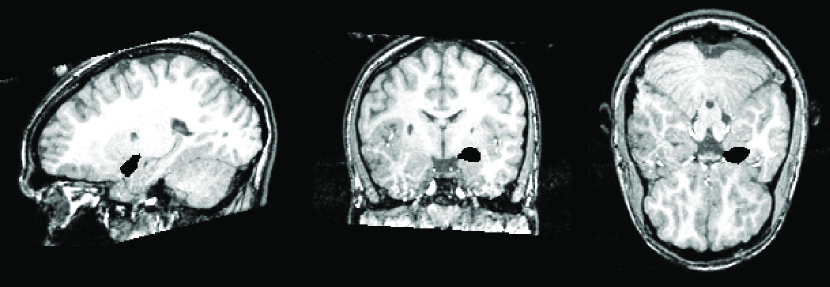

MRI depends on the response of magnetic fields in generating digital images that provide structural information about brain noninvasively. Compared to the computed tomography (CT), MRI has been mainly used for in vivo imaging of the brain due to higher image contrast in soft tissues. Unlike CT, MRI does not use X-ray for imaging so there is no risk of radiation exposure. MRI produces images based on the spin-lattice relaxation time (T1), the spin-spin relaxation time (T2) and the proton density () (Bernstein et al., 2005). The widely used T1- and T2-weighted imaging weight the contribution of one component and minimize the effect of the other two. The T1-weighted MRI is more often used in anatomical studies compared to the T2-weighted MRI. Structural images you are seeing are most likely T1-weighted MRI.

Figure 2 shows an example of MRI and the manual segmentation of the left amygdala, which is colored in black. This manual segmentation is stored as a binary image consisting of 0’s and 1’s. In MATLAB, to read the header file, we invoke the command